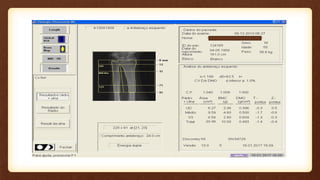

O documento discute a densitometria óssea do antebraço, recomendando mensurar o antebraço dominante devido apresentar maior densidade óssea. Aponta que aparelhos podem se referir à mesma região do antebraço por nomenclaturas diferentes, levando a aquisições e análises incorretas.